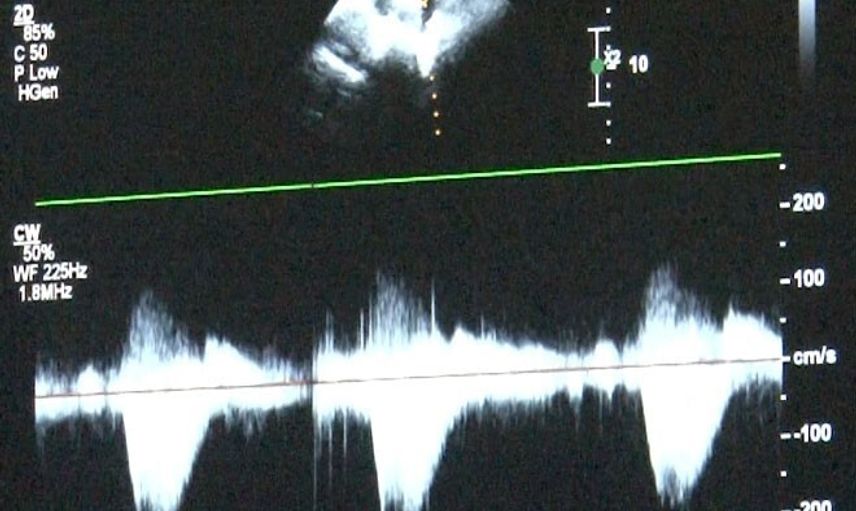

Türkiye'de doğan bebeklerin bir kısmı doğumsal kalp hastalıkları ile dünyaya gelmekte. Dr. Damla Gökçeer Akbulut, doğumsal kalp hastalığı teşhisi için zamanında tetkiklerin yapılmasının yaşamsal öneme sahip olduğunu belirtiyor. "Anne karnındaki fetal ekokardiyografi ile erken tespit mümkün," dedi.